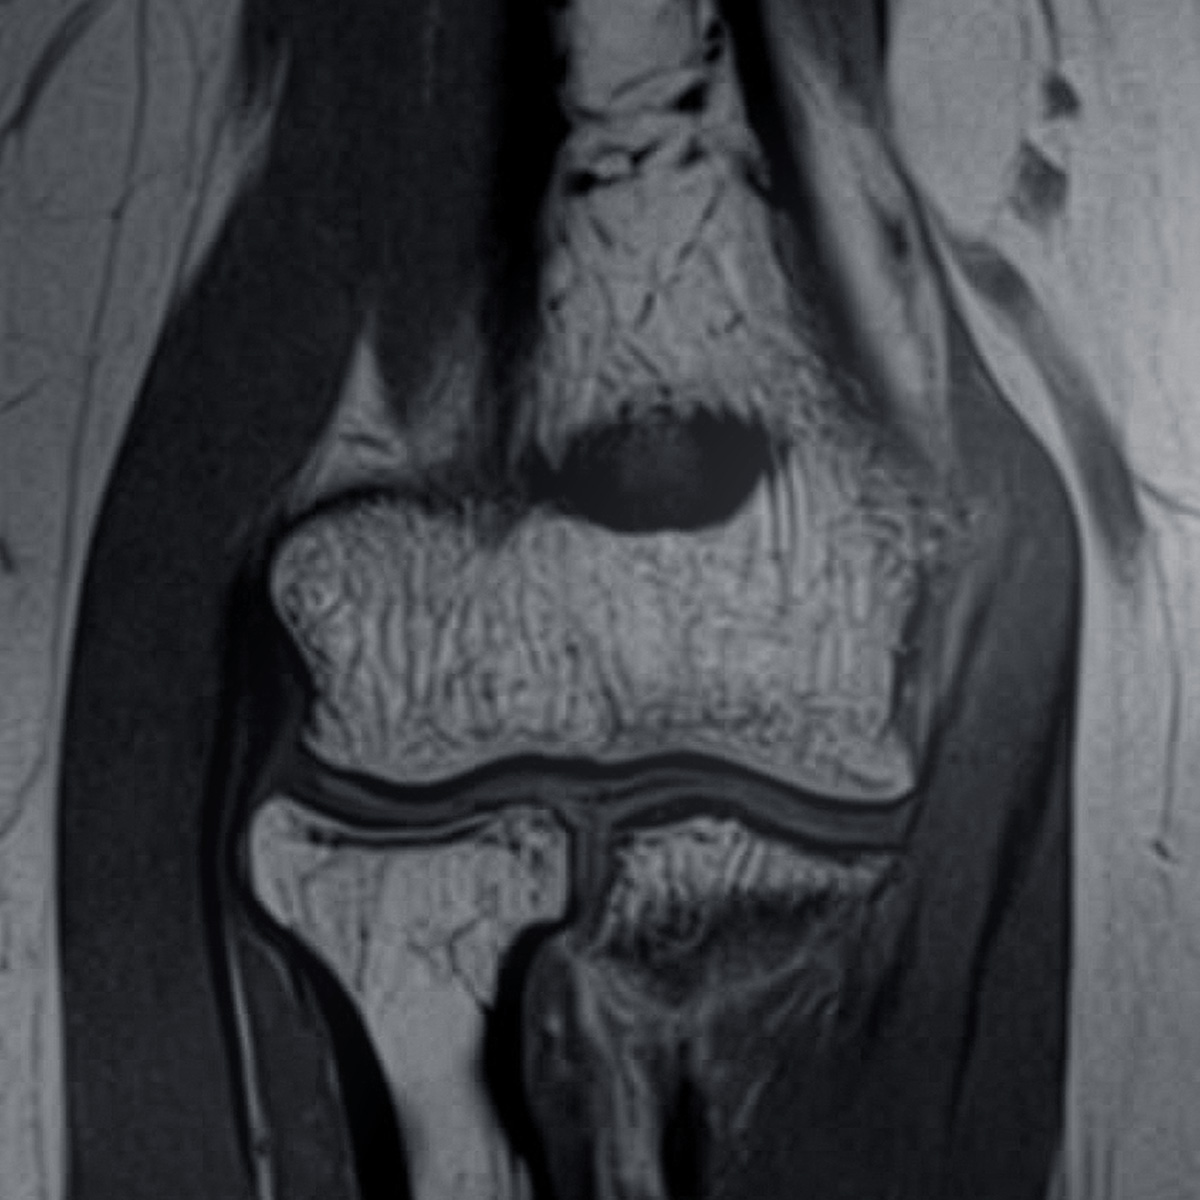

Magnetic resonance imaging is the most accurate and reliable imaging method for diagnosing pain and problems in the elbow or forearm.

The condition of the cartilage of the articular surfaces in the elbow joint can also be accurately assessed. MRI is always the preferred method for examining the tendons and ligaments of the elbow joint.

It is the best way of detecting suspected biceps tendon ruptures.